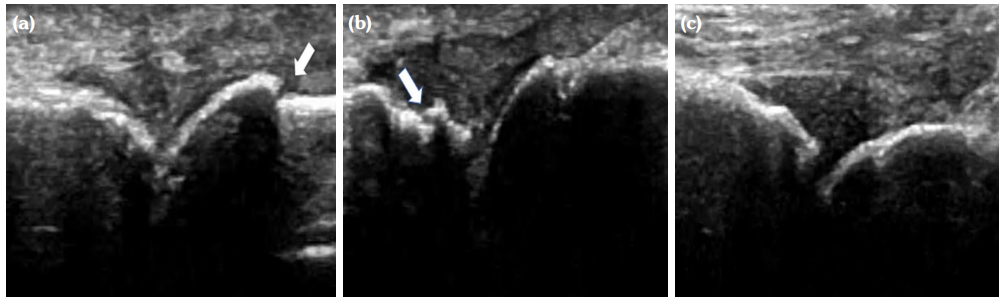

The degree of BE and synovial hyperplasia in SNRA or SPRA is more serious, and the blood flow signal is more abundant. However, the degree of synovial hyperplasia in osteoarthritis was mild, and no obvious blood flow signal was detected (Figures 1, 2, 3 and 4). Magnetic resonance imaging (MRI) studies of SPRA also showed serious BE (Figure 5).

Among SNRA, SPRA and non-RA, there was no significant difference in the grades of SH, PD, BE, nor the number of cases of tendinitis and tenosynovitis between the SNRA group and the SPRA group (p>0.05) (Table 3). There were, however, statistically significant differences in the number of cases of SH1, SH3, PD and BE grades between the SNRA and non-RA groups (p<0.001). There was no significant difference in the number of cases of SH2, PD2, tendinitis or tenosynovitis between the SNRA and non-RA groups (p>0.05) (Table 4).

Several previous studies have proposed that PD grading has a potent specificity for the early evaluation of SPRA patients. Nam et al.[14] proposed that, in the MCP, PIP and metatarsophalangeal joints of subclinical SPRA patients, the joints with PD Grade ≥2 had a poor prognosis. Kawashiri et al.[15] suggested that, in the wrist joints of SPRA patients, the prevalence of MRI-detected bone marrow edema in joints with PD Grade ≥2 under ultrasound was much higher than that in PD Grade ≤1 joints. In this study, we report that there was no significant difference in the clinical features and ultrasound findings of SPRA and SNRA patients in the early onset, and that the condition of PD Grade ≥2 had the same high specificity for the early diagnosis of SNRA as SPRA. Combined with a BE Grade ≥2, this may help to improve the sensitivity of ultrasonographic diagnostic measures and can achieve an optimal balance between high sensitivity and high specificity.

Our findings suggest that the use of synovial blood flow and the degree of BE are helpful in distinguishing RA from non-RA, which may be explained by the underlying pathological changes. The pathological features of RA include primary synovial inflammation, which produces aggressive synovial pannus attached to the cartilage, causing hypoxia and erosion of the bone. Synovitis caused by non-RA disease is mostly due to inflammation, edema and thickening of synovium due to degenerative or pathological changes of cartilage and cortical bone. It is not difficult to understand that the invasive synovial blood vessels during RA are closely related to the phenomenon of BE; thus, the combination of the two ultrasonic characteristics are sound pathological indicators for the evaluation of RA.